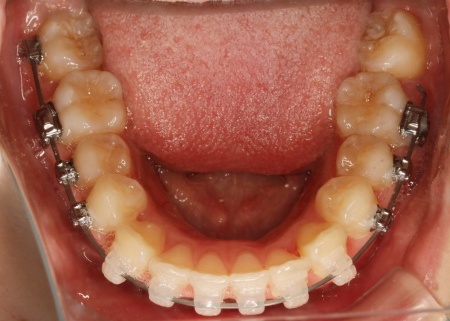

・ワイヤー矯正

歯の表面にブラケットと呼ばれるボタン状の装置を接着し、そこにワイヤーを通して歯を移動させる方法です。

患者様は目立たない治療方法を望まれていたため、ブラケットには白く目立ちにくい「セラミックブラケット」を選択しました。

まずは歯の表面にセラミックブラケットを装着し、ワイヤー矯正で歯を全体的に移動させます。

歯並びがある程度正しい位置に並んだら、マウスピース矯正で微調整を行いました。